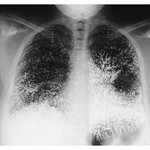

[아리]

수은

먹고 자살 시도한 여자의 엑스레이

[추억파리여]